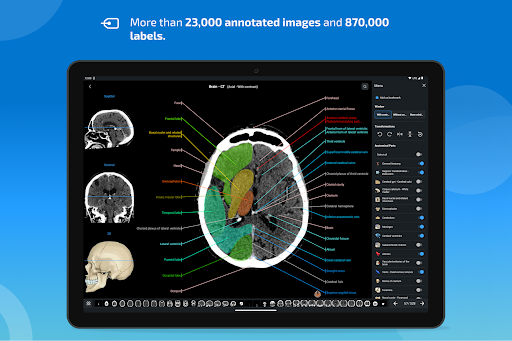

- عرض التشريحية يعرض الآن المزيد من التسميات

- يمكنك الآن إخفاء الهياكل واحداً تلو الآخر (زر جديد داخل نافذة الوصف المنبثقة) وعرضها مرة أخرى في القائمة الصحيحة